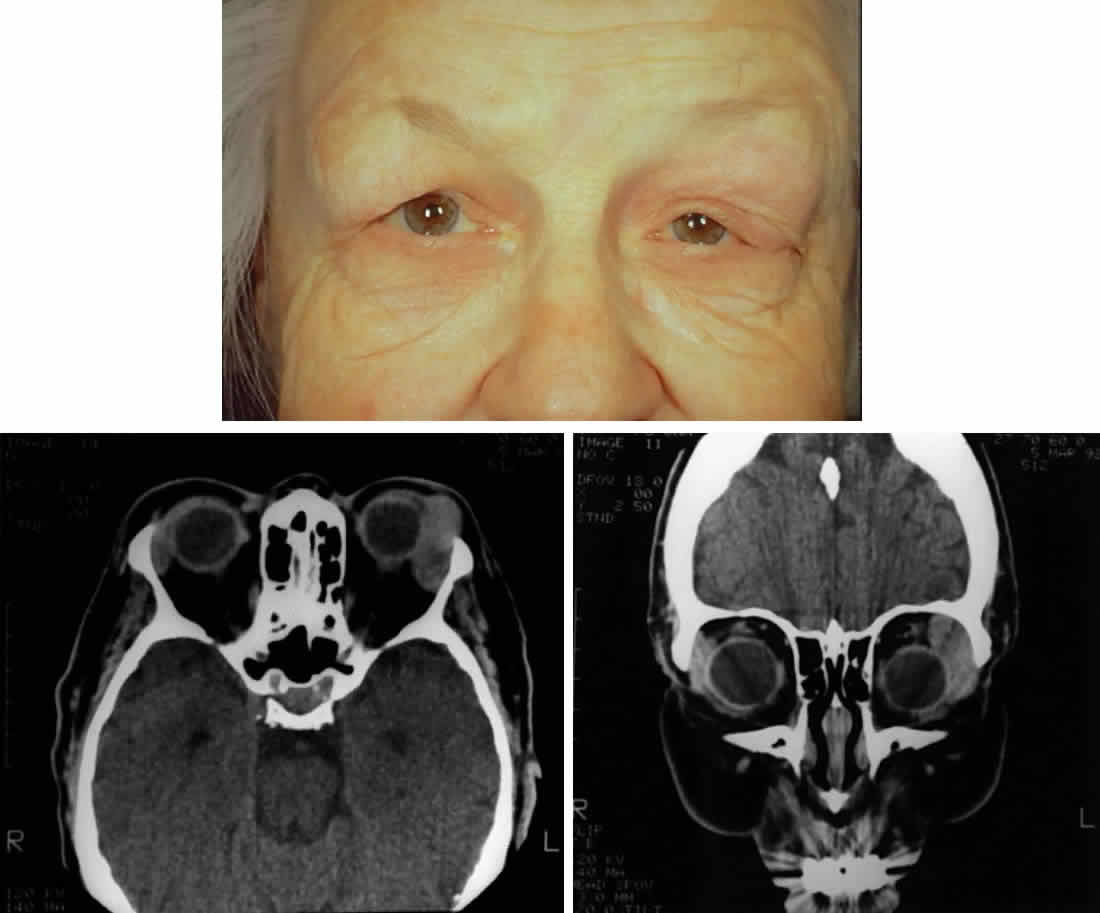

Lacrimal gland fossa lesions usually present with fullness of soft-tissue structures in the area of lacrimal gland fossa. Typically, this appears as an “S-shaped” contour of the upper eyelid (Fig. 2A) or as asymmetry of the superior sulci. In addition, ipsilateral blepharoptosis may be present. Table 2 lists other findings associated with lacrimal fossa lesions.

Fig. 2. A 68-year-old woman with malignant lymphoma. A. Clinical photograph demonstrating fullness over the left lacrimal gland fossa, S-shaped contour of the upper eyelid, asymmetric superior sulci, and ptosis. Inflammatory signs are absent. B. Axial computed tomograph demonstrating the classic well-demarcated, oblong appearance of lymphoproliferative diseases of the lacrimal gland. Note that the lesion extends beyond the anterior orbital rim. C. Coronal computed tomograph of the same lesion. Note that the lesion contours to the globe and bone and does not produce any bone changes.

In patients with lymphoproliferative infiltration of the lacrimal gland, a firm, rubbery mass is often palpable in the lacrimal gland fossa. In contrast to inflammatory lesions, lymphoid lesions are usually not tender. Lymphoid lesions contour to the shape of the fossa and surrounding structures, producing a well-demarcated, oblong mass on computed tomography (see Figs. 2B and 2C).9,31 Prominent enhancement after intravenous administration of contrast material is typical for lymphoid lesions.31 The amount of enhancement is similar to enhancement of extraocular muscles. Anterior extension beyond the orbital rim indicates palpebral lobe involvement, which is more typical of lymphomatous lesions and very rare for epithelial tumors of the lacrimal gland.30 In addition, destruction of bone is rare with lymphomatous lesions and therefore is useful in distinguishing lymphomatous lesions from malignant epithelial tumors.9